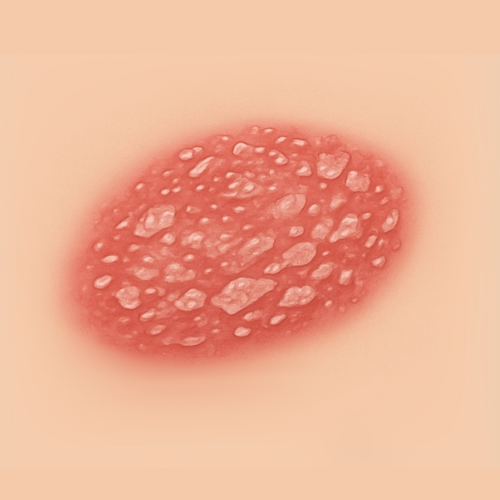

Find Relief by Symptom or Skin Concern

EMUAID is designed to relieve symptoms from over 100 difficult-to-treat conditions like eczema, psoriasis, nail fungus, hemorrhoids, shingles, acne, rashes, burns, cellulitis, and more. If it's red, itchy, cracked, painful, or inflamed- EMUAID may help.